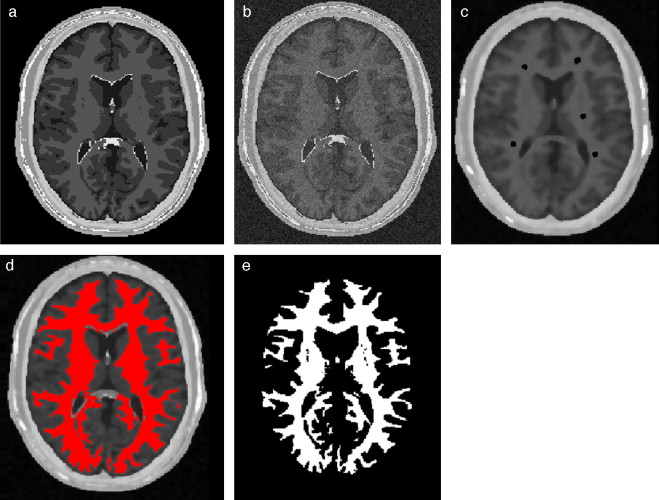

En la figura 10 se presenta el resultado de segmentar la materia blanca del cerebro en IRM empleando la rutina de Region Growing mencionada. En la figura 10 .a se observa la vista 3D del volumen inicial. En la figura 10 .b se observa uno de los cortes de la figura 10 .a con la selección de cuatro semillas iniciales de forma esférica dentro de la zona de la materia blanca. En la figura 10 .c se observa en color rojo la zona región de la materia blanca obtenida al finalizar la rutina de segmentación. En la figura 10 .d se presenta una vista 3D de la zona de la materia blanca segmentada.

Segmentación de materia blanca empleando Region Growing en IRM del cerebro. (a) ...

Figura 10.

Segmentación de materia blanca empleando Region Growing en IRM del cerebro. (a) Volumen formado por varios cortes de IRM cerebral original. (b) Vista de un corte coronal con la lección de cuatro semillas iniciales. (c) Vista del corte coronal (b) con la materia blanca segmentada con Region Growing . (d). Vista volumétrica de la materia blanca segmentada en (c).

En la figura 20 se presentan los resultados obtenidos por cada etapa en imágenes médicas de IRM del cerebro en formato DICOM, 60 slices , tamaño de 256 × 256 pixels, voxel spacing: 0,86 × 0,86 mm × 3,0 mm . Por efectos de visualización, solamente se presenta uno de los cortes axiales utilizados. Obsérvese en la figura 20 .b la selección de cuatro semillas sobre la zona de interés, las cuales fueron asignadas de manera arbitraria. El éxito de la segmentación dependerá del lugar donde se coloquen estas semillas.

Figura 20.

Segmentación de materia blanca empleando Region Growing en IRM del cerebro. (a) Volumen de IRM cerebral original. (b) Vista de un corte axial con la lección de cuatro semillas iniciales. (c) Imagen (b) filtrada con difusión anisotrópica. (d) Vista del corte axial (b) con la materia blanca segmentada a través de Region Growing . (e). Vista volumétrica de la materia blanca segmentada en (d).